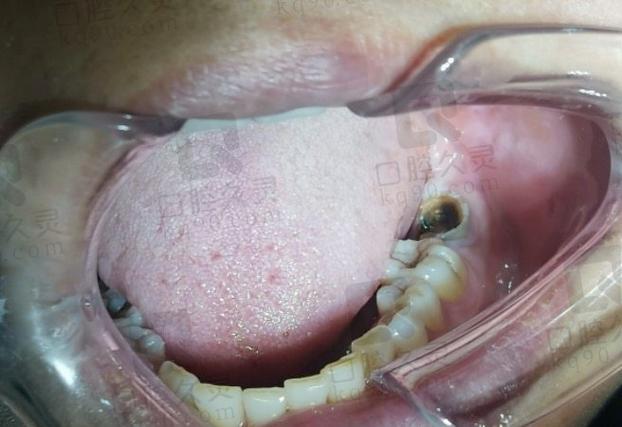

拔牙窝内不能有急性炎症(如根尖周脓肿、牙周脓肿),感染会严重影响种植体骨结合的成功率,如果存在慢性感染(如根尖周炎、牙周炎),通常需要先进行彻底的感染控制治疗(如根管治疗、牙周刮治等),待炎症完全消退后才能考虑种植,或者进行严格的清创处理。

(图片来源网络,侵删) -